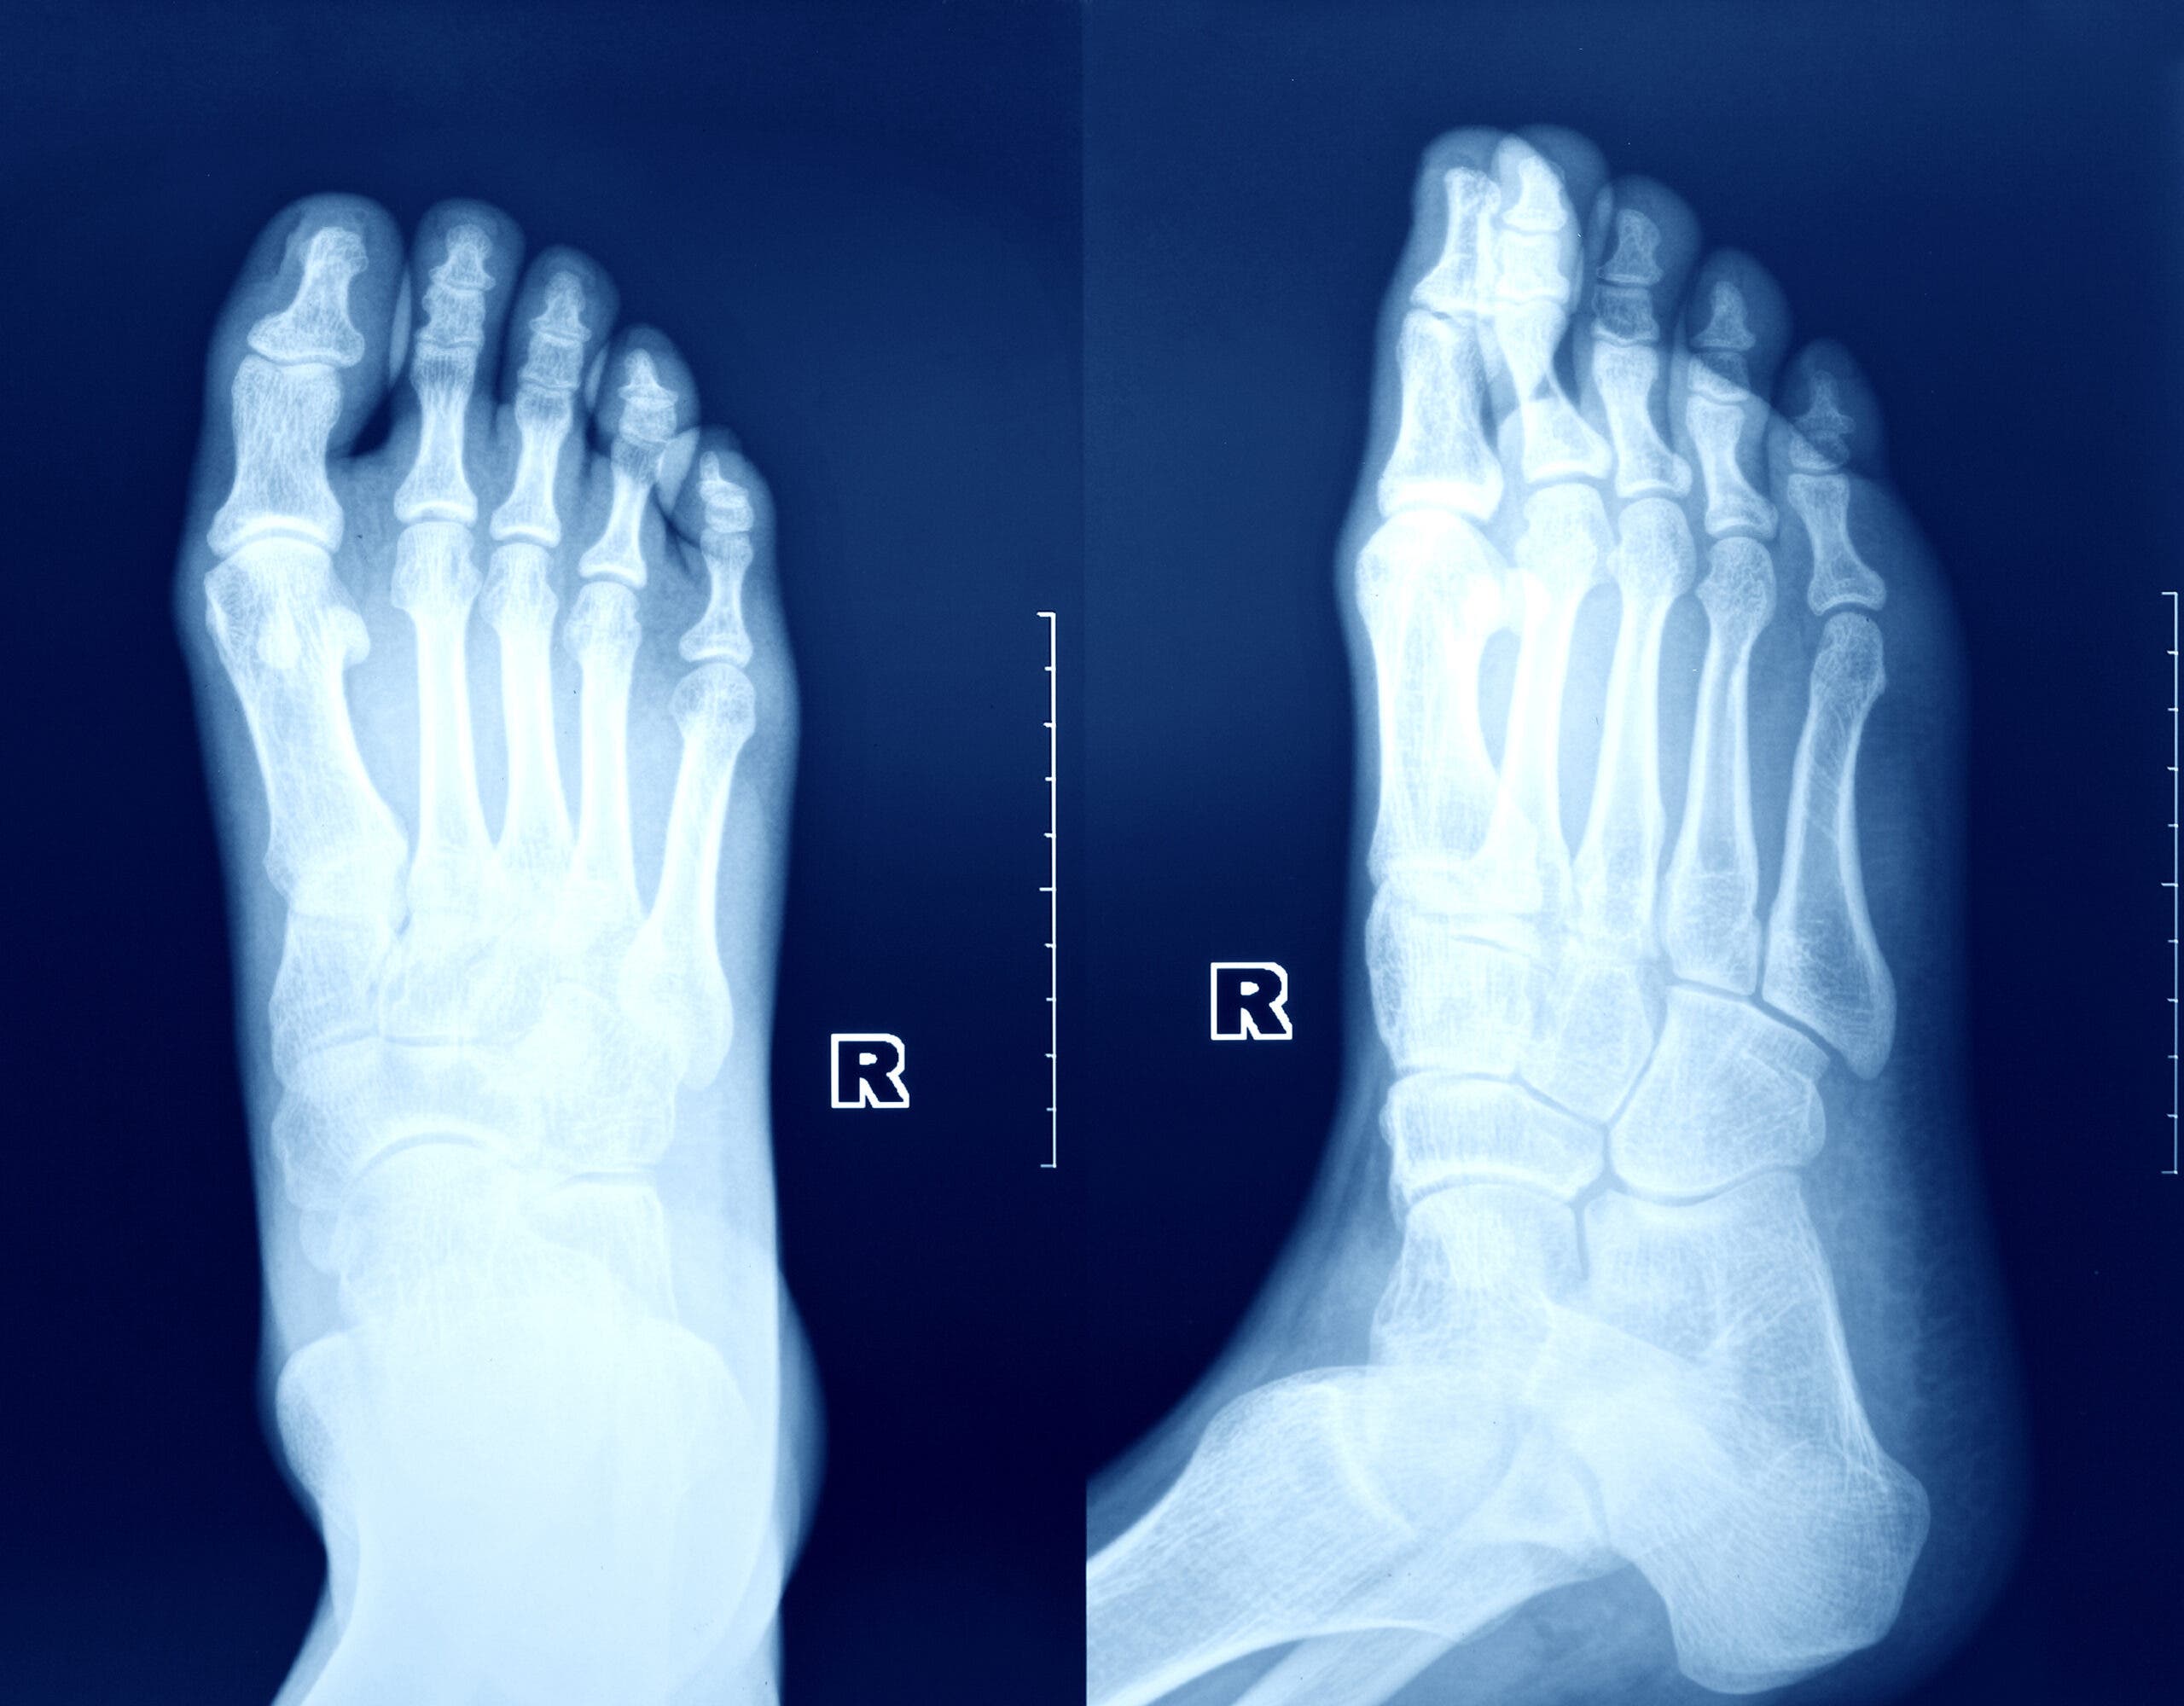

If you think you might have a bone stress injury, stop high-impact, provocative (namely, running) activities, and call your doctor – you can’t “train through” a bone stress injury. Often, x-rays are the first imaging test performed, although they have low sensitivity for detecting bone stress injuries, as only more advanced injuries with distinct fracture lines or calluses will be seen. Bone scans are sensitive to detecting activity in bones, but are unable to directly visualize the degree of injury. MRIs, then, are considered to be the gold standard for imaging bone stress injuries, as they can show periosteal reactions, bone marrow edema, and fracture lines, and can help to determine the severity of the injury. Bone stress injuries can be assigned “grades” based on MRI findings, which can assist with determining overall prognosis and healing time, as well.